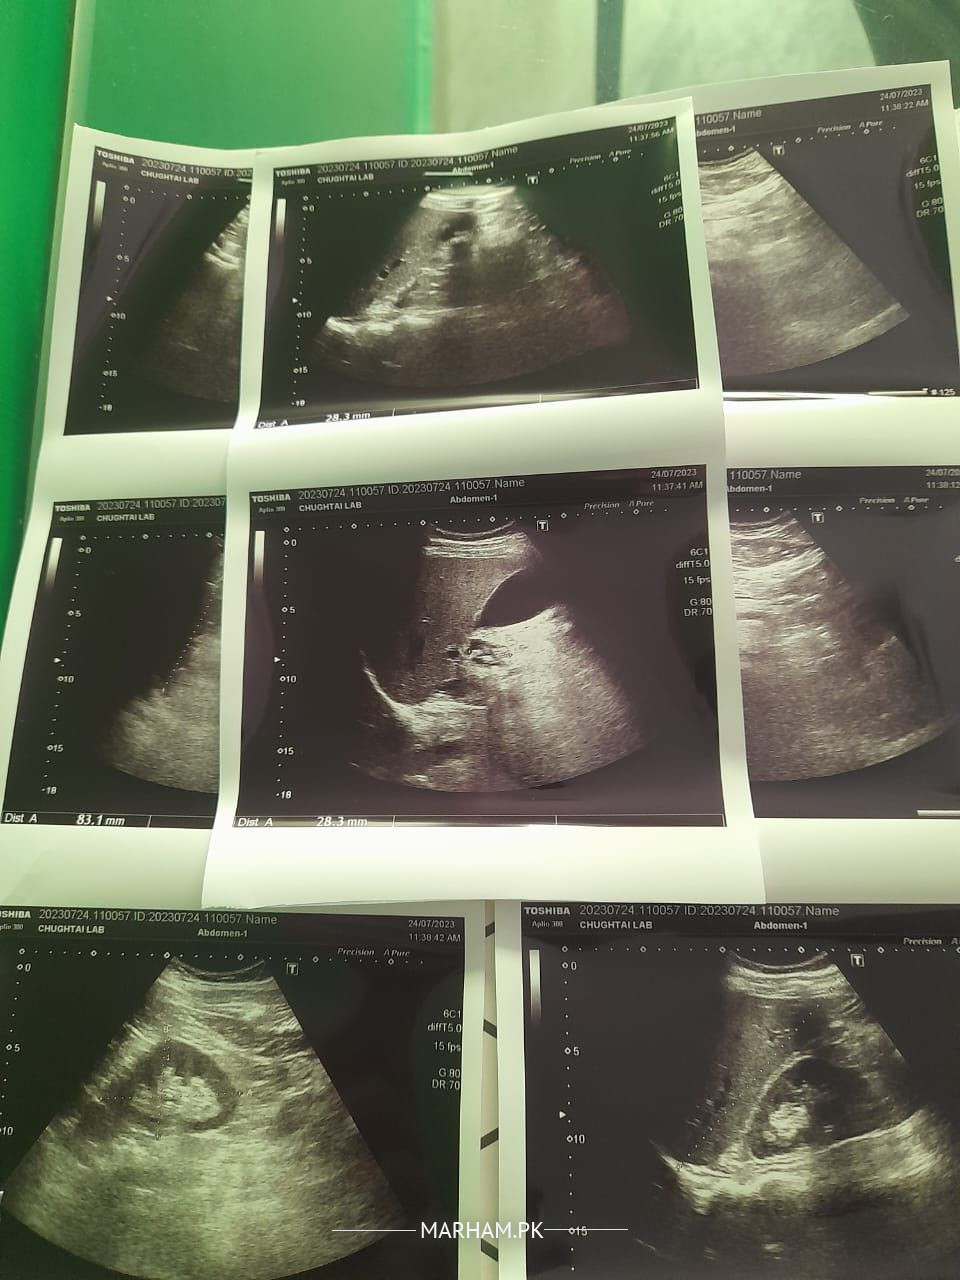

my husband suffered from severe pancreatitis 3 years ago. he was diagnosed with sand like stones in gall blader. doctor suggested him not to go for operation untill he suffer from pain. now he is feeling light pain but doctor says it is stomach pain other doctor said go for operation now please any gastroentologist plz see these reports and suggest what to do

This is a silent gall stone. at present. But, he will need surgery to avoid complications associated with gall stone.

Get it operated ,second Attack of pancreatitis can be devastating